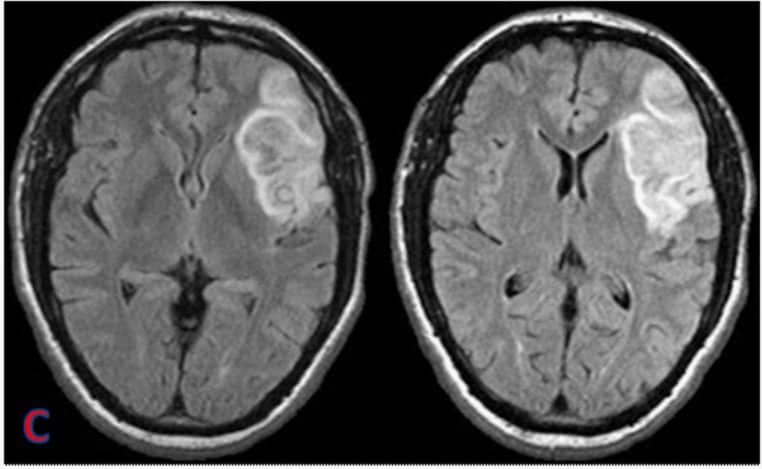

Micro-hémorragies : de petites traces sur l’IRM, un grand signal d’alarme

Les micro-hémorragies cérébrales sont de minuscules dépôts de sang visibles à l’IRM. La plupart du temps, elles ne déclenchent aucun symptôme immédiat. Elles n’en sont pas moins importantes : chez les personnes âgées, leur nombre augmente avec l’âge et s’associe à un risque majoré d’AVC et de déclin cognitif.

C’est là que l’étude de JAMA Network Open interpelle : chez les 1 441 participants atteints d’apnée du sommeil modérée à sévère, ces micro-saignements sont plus fréquents que chez des personnes sans apnée, et l’écart persiste même après avoir neutralisé statistiquement l’âge, le sexe, l’IMC, la tension artérielle, le diabète et les lipides.

En clair : les micro-coupures respiratoires de la nuit ne se contenteraient pas d’abréger le sommeil, elles laisseraient aussi des empreintes vasculaires dans le cerveau. Elles ne provoquent pas une démence à elles seules, mais elles installeraient un terrain moins favorable à la mémoire et à l’attention.

En apnée obstructive, les voies aériennes se referment et l’oxygène sanguin chute. Ces hypoxies intermittentes, répétées nuit après nuit, déclenchent des réponses inflammatoires et vasculaires. Sur le cerveau, elles se traduisent par un stress oxydatif, des atteintes de la paroi des petits vaisseaux et, au fil du temps, par des micro-hémorragies visibles en imagerie.